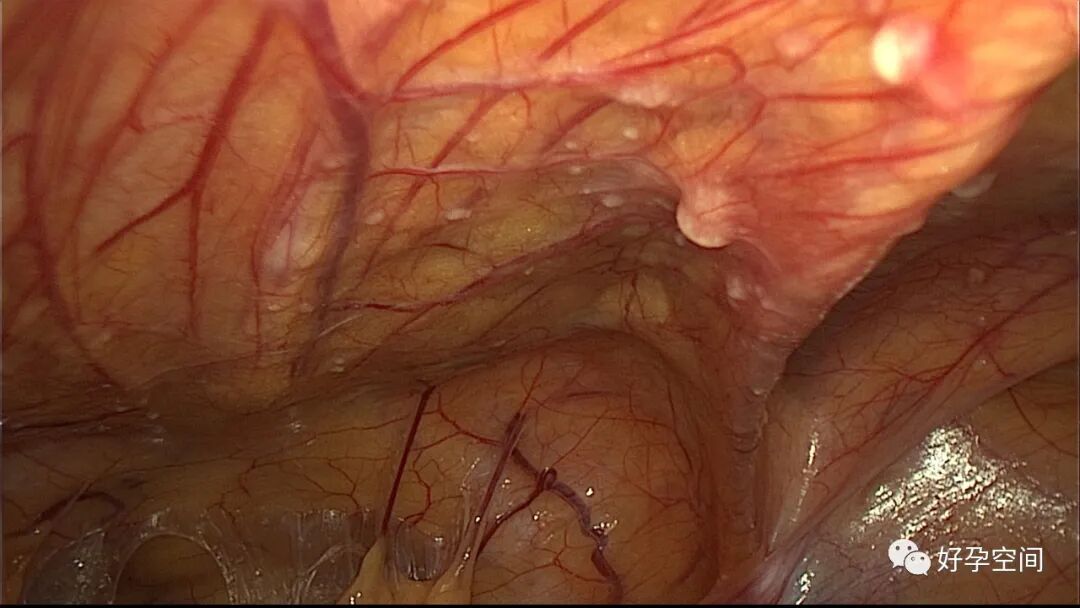

病例1:患者24岁,原发不孕,造影示双侧输卵管堵塞,否认结核病史,无结核病家族史。2022年4月以不孕症收入院手术,术前化验检查无明显异常,胸片示左肺下叶内带稍高密度结节影。行宫腹腔镜探查,宫腔被覆一层棉絮状质脆增生组织,宫腔狭小,宫壁僵硬。腹膜及大网膜广泛分布粟粒样结节,左侧输卵管充满干酪样组织及灰色脓液。

子宫内膜结核是由结核分枝杆菌在子宫内膜部位种植引起的炎症,是仅次于输卵管结核的常见女性生殖器结核。子宫内膜结核常由输卵管结核蔓延而来,多继发于盆腔腹膜结核或肺结核。子宫内膜结核的超声表现主要为:子宫内膜回声不均匀、宫腔内结节样病灶、宫腔内强回声灶、单纯的子宫内膜薄等。盆腹腔超声显示输卵管炎性表现:输卵管增粗、肥厚、扭曲、僵硬、输卵管积液积脓、卵巢旁混合性包块、输卵管系膜囊肿、盆腔包裹性积液等。术中所见:盆腹腔组织粘连、盆腹腔粟粒样结节、结核球、脓肿等,输卵管伞端烟斗样外翻,输卵管内充满淡黄色干酪样或豆渣样组织。宫腔镜显示宫腔狭窄、宫壁僵硬、宫内膜肉芽肿样增生、内膜质脆易刮除、干酪样组织、脓液等。